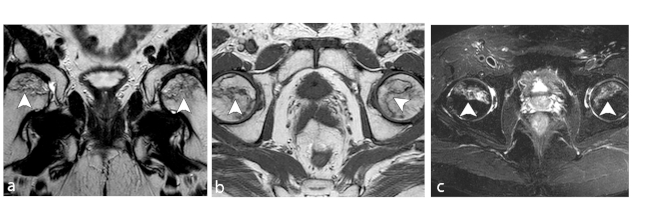

El patrón más común de la ON es la médula amarilla en la epífisis rodeada de una línea de morfología en anillo o en cuña, de baja señal en todas las secuencias en relación a la formación de tejido esclerótico (►Fig. 1). Además, en estos casos se puede observar el signo de doble línea, en relación a otro anillo profundo hiperintenso en secuencias ponderadas en T2, correspondiente a tejido de granulación en remodelación.6,10

Existen varias escalas para determinar el grado de severidad de la ON de cadera mediante hallazgos imagenológicos con el fin de identificar y guiar el tratamiento adecuado, siendo las clasificaciones de Fitcat y Arlet, y/o Steinberg (►Tablas 2 y 3) las más utilizadas por los radiólogos al evaluar la progresión, desde la enfermedad radiológicamente negativa hasta el colapso de la cabeza femoral con desarrollo secundario de osteoartritis (►Figs. 2 y 3).6 Es de conocimiento que la importancia clínica de la ON depende casi por completo de la probabilidad de colapso articular, por lo que el volumen de la cabeza femoral afectada sería su predictor más relevante.

En RM en secuencia ponderada en T1, la intensidad de señal de la grasa de la médula ósea del cóndilo femoral afectado es reemplazada por un área con baja señal, asociada a una periferia de aún más baja señal (►Figs. 4 y 5).8 En la secuencia ponderada en T2 se visualiza lesión central hipointensa con área de señal alta periférica en relación al patrón de edema de la médula ósea (►Fig. 6).11